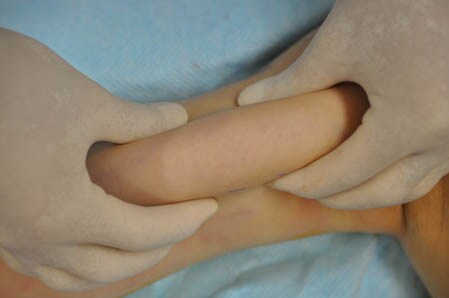

上の画像の部分をつまんでみましょう。

↓ ↓ ↓